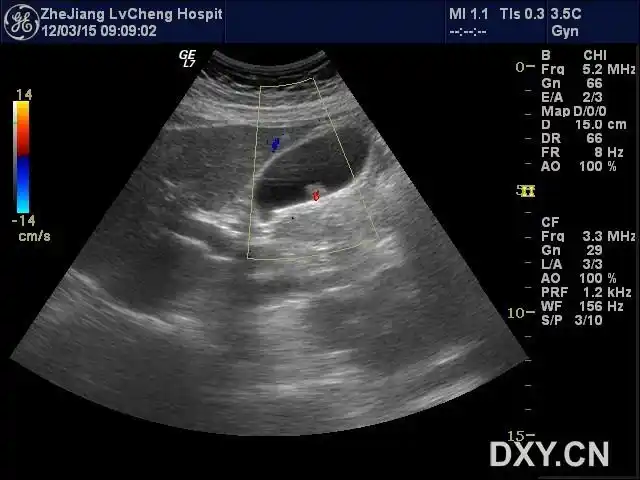

考虑急性坏疽性胆囊炎伴穿孔可能——zengerya - 超声医学讨论版

诊断 坏疽性胆囊炎伴穿孔 病例要点 超声上,复杂性或坏疽性胆囊炎可能

气肿性胆囊炎超声表现为胆壁非游离面或腔内出现强回声(气体), 伴有